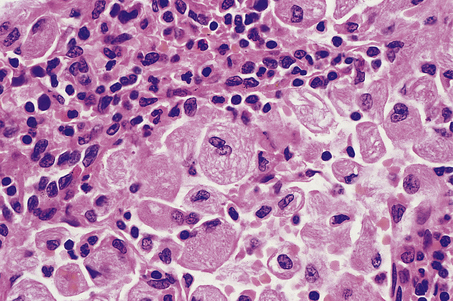

Microscopically, affected lymph nodes show a partial or complete effacement of their normal architecture by a mixed infiltrate containing lymphocytes, histiocytes, plasma cells and eosinophils as well as the malignant cells of classical Hodgkin’s lymphoma; these are large cells and take the form of mononuclear Hodgkin’s cells or of Reed–Sternberg cells, which have a large, pale, multilobed nucleus and a prominent eosinophilic nucleolus about the size of a red blood cell (Fig. 22.7).

image

Fig. 22.7 Hodgkin’s lymphoma. image A classical Reed–Sternberg cell shows multiple nuclei with prominent nucleoli. image Reed–Sternberg cells identified by immunohistochemical staining for CD30 (Ki-1 antigen).